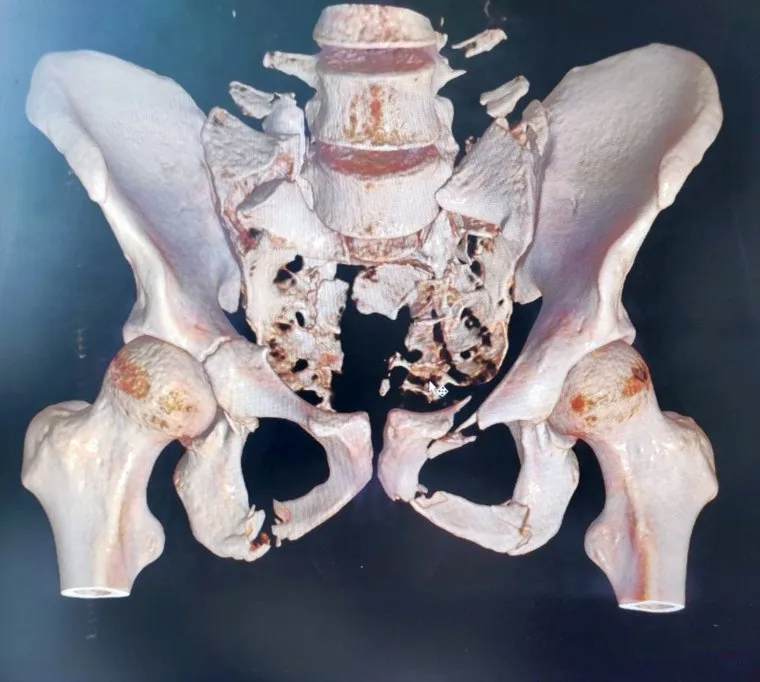

В курганском Центре им. Илизарова прооперировали пациента со сложной травмой таза и позвоночника, возникшей из-за падения с большой высоты. Сразу после травмы молодой человек потерял подвижность, но благодаря реконструкции таза он начал садиться и вставать, сообщили в пресс-службе медицинского центра.

«Экстраординарный клинический случай в практике врачей Центра Илизарова. В клинику реконструктивной хирургии повреждений конечностей и таза поступил 24-летний пациент из г. Тобольска, у которого таз был оторван от позвоночника. Пациенту провели сложное многоэтапное хирургическое вмешательство по реконструкции тазового кольца и крестцового отдела позвоночника. Выполнили надежную фиксацию позвоночника и таза. Операция шла около 6 часов», — говорится в сообщении Центра Илизарова.

Молодой человек упал с 4-го этажа своего дома в Тобольске. После травмы таз и тело пациента между собой были связаны только мышцами, он не мог двигаться. В больнице Тобольска ему провели первичную стабилизацию костей таза и переломов ног аппаратами внешней фиксации. Учитывая сложность травмы, мужчину направили в курганский медцентр. Как только курганские врачи связали таз с позвоночником, мышцы заработали, парень начал поворачиваться, садиться и даже вставать. Сейчас пациент находится под наблюдением, врачи дают хорошие прогнозы на восстановление.